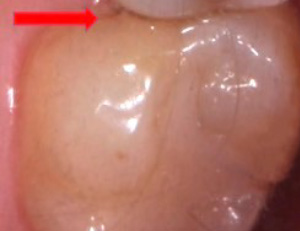

こちらは、1年受診控えされていた方のレントゲンの写真とお口の中の写真です。

コロナ前までは検診も3ヶ月に一度はご来院されていた方ですが、コロナが心配でしばらく受診できていなかった1年のうちにかなり虫歯が進行してしまっています。左のレントゲン写真の矢印で指している黒い部分が虫歯です。

ただ、お口の中の写真では、穴になっているわけではないので虫歯が進行しているのが非常に分かりづらいです。

こうなる前の浅い虫歯のうちに早期発見早期治療できるように、かかりつけの歯科医院を見つけて少なくとも3ヶ月に一度は検診を受けることをおすすめします。